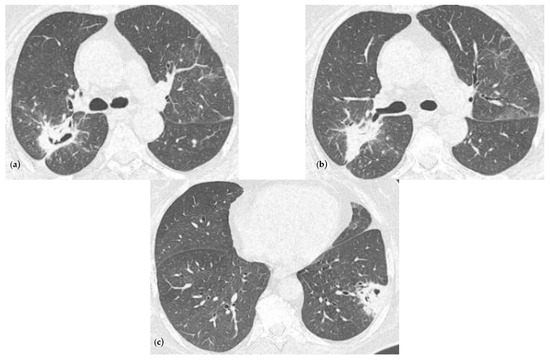

2.2. Blood Workup, Functional Tests, Bronchoscopy, and Radiological Findings

2.3. Treatment and Monitoring

2.4. Follow-Ups